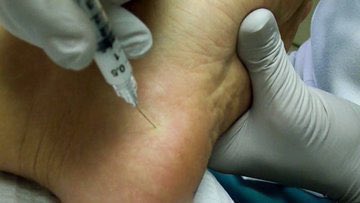

#شوكة_القدم

♦️الحقن الكورتيزون الموضعية تخفف حدة الالتهاب ومن ثم تقلل الالم

♦️في بعض الحالات التي لا تستجيب لطرق العلاج المختلفة،

يلجأ الى التدخل الجراحي